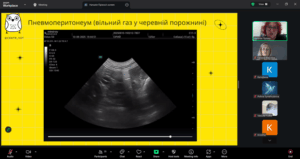

Лектор – Наталія ПРІХНО, яка є кардіологом, лікарем з УЗД даної ветеринарної клініки, розповіла про те, як правильно працювати з УЗД-апаратом, на що звертати увагу під час обстеження котів і собак та які «підводні камені» можуть чекати під час інтерпретації зображень. Було багато корисних порад і реальних випадків з практики — саме те, що найбільше цінують слухачі. Пані Наталія детально пояснила принципи проведення AFAST/TFAST, ключові орієнтири обстеження та їхнє значення у клінічній практиці. Учасники мали змогу ознайомитися з типовими патологіями, які можуть бути виявлені за допомогою цих протоколів, а також з поширеними діагностичними помилками та способами їх уникнення. Окрему увагу було приділено практичним клінічним випадкам, що продемонстрували ефективність AFAST/TFAST у швидкій оцінці стану тварини, прийнятті рішень у невідкладних ситуаціях та моніторингу динаміки стану пацієнта.